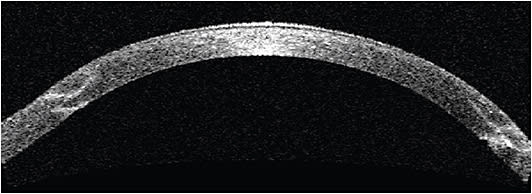

That said, a complete comprehensive ophthalmic exam should be initiated before managing post-PK corneal astigmatism to eliminate any non-corneal cause for poor vision. Furthermore, understanding uncorrected visual acuity (UCVA), best spectacle-corrected visual acuity (BsCVA), and best contact lens-corrected visual acuity (BcCVA) are all important in deciding which corrective method to utilize. Other key factors, in addition to manifest refraction, include corneal topography, keratometry, corneal pachymetry, and cycloplegic refraction in pediatric patients (Figure 1).